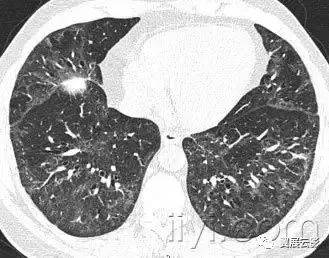

十九、肺实变:

病理学:肺实变是指渗出,或者其他疾病成分替代肺泡内气体,导致肺实变。

平片和CT:肺实变表现为肺实质密度的均匀一致性增高,导致肺血管和气道壁边缘不清。有时可见含气支气管征。只有在极少数的情况下,肺实变的密度变化有助于鉴别诊断,例如脂性肺炎是密度减低,胺碘酮中毒时密度增高。

图示为多灶性的肺实变。